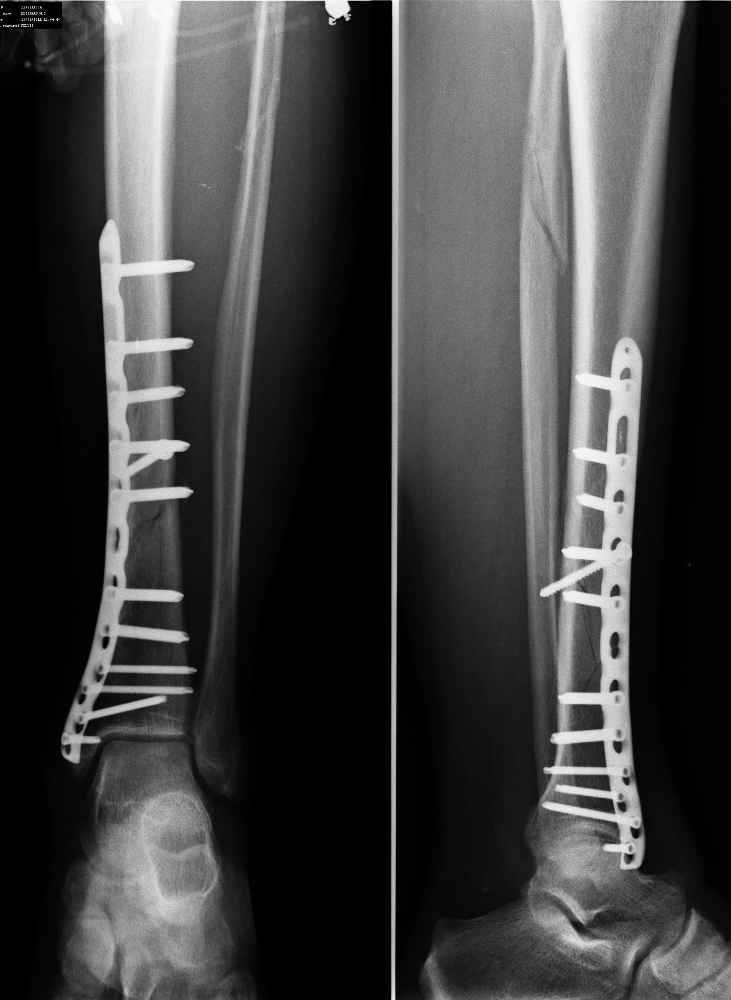

А что беспокоит пациента? При остеосинтезе пластинами LCP в проксимальном и дистальном отломках нужно было ввести в 2 раза меньше винтов. Если сейчас удалить часть винтов и дать частичную нагрузку на ногу, то я думаю процес консолидации пойдет веселее.

Отломки идеально сопоставлены. Остеосинтез стабильный. В такой ситуации должно наступать первичное сращение практически без образования мозоли. Ориентироваться при оценке степени консолидации нужно на завуалированность линий перелома и нарастание, при неблагоприятном развитии ситуации, регионарного остеопороза, которого пока нет, а не на наличие и величину костной мозоли. И нагрузку через такой срок можно уже практически полную давать.

согласен с Михаилом, надо дать дозированную нагрузку, это улучьшит питание конечности. А кость надо жалеть и столько не крутить винтов, шанс на атрофический ложняк велик. Стягивающий 4,5 мм винт не работает, а 5,0 мм LSP распирает линию перелома.

За свой не богатый опыт работы, я не видел явных признаков сращения б/б через 9 нед. Как Вы оперировали: открытый остеосинтез (межфрагментарный винт этому доказательство) или непрямой остеосинтез (мостовидная пластина и из разреза-прокола винт)?

Остеосинтез достойный. Единственное не стоит оставлять пустое отверстие в проекции перелома, но к данному вопросу это никакого отношения не имеет. Нагрузка, динамическое наблюдение.

о замедленной консолидации говорить однозначно рано, беспокоиться практически не о чем

Ложка дегтя:

самый дистальный шуруп насквозь через внутреннюю лодыжку в сустав ( см увеличенный рисунок). Хорошо было бы его убрать - стабильности остеосинтезу он совершенно не добавляет.